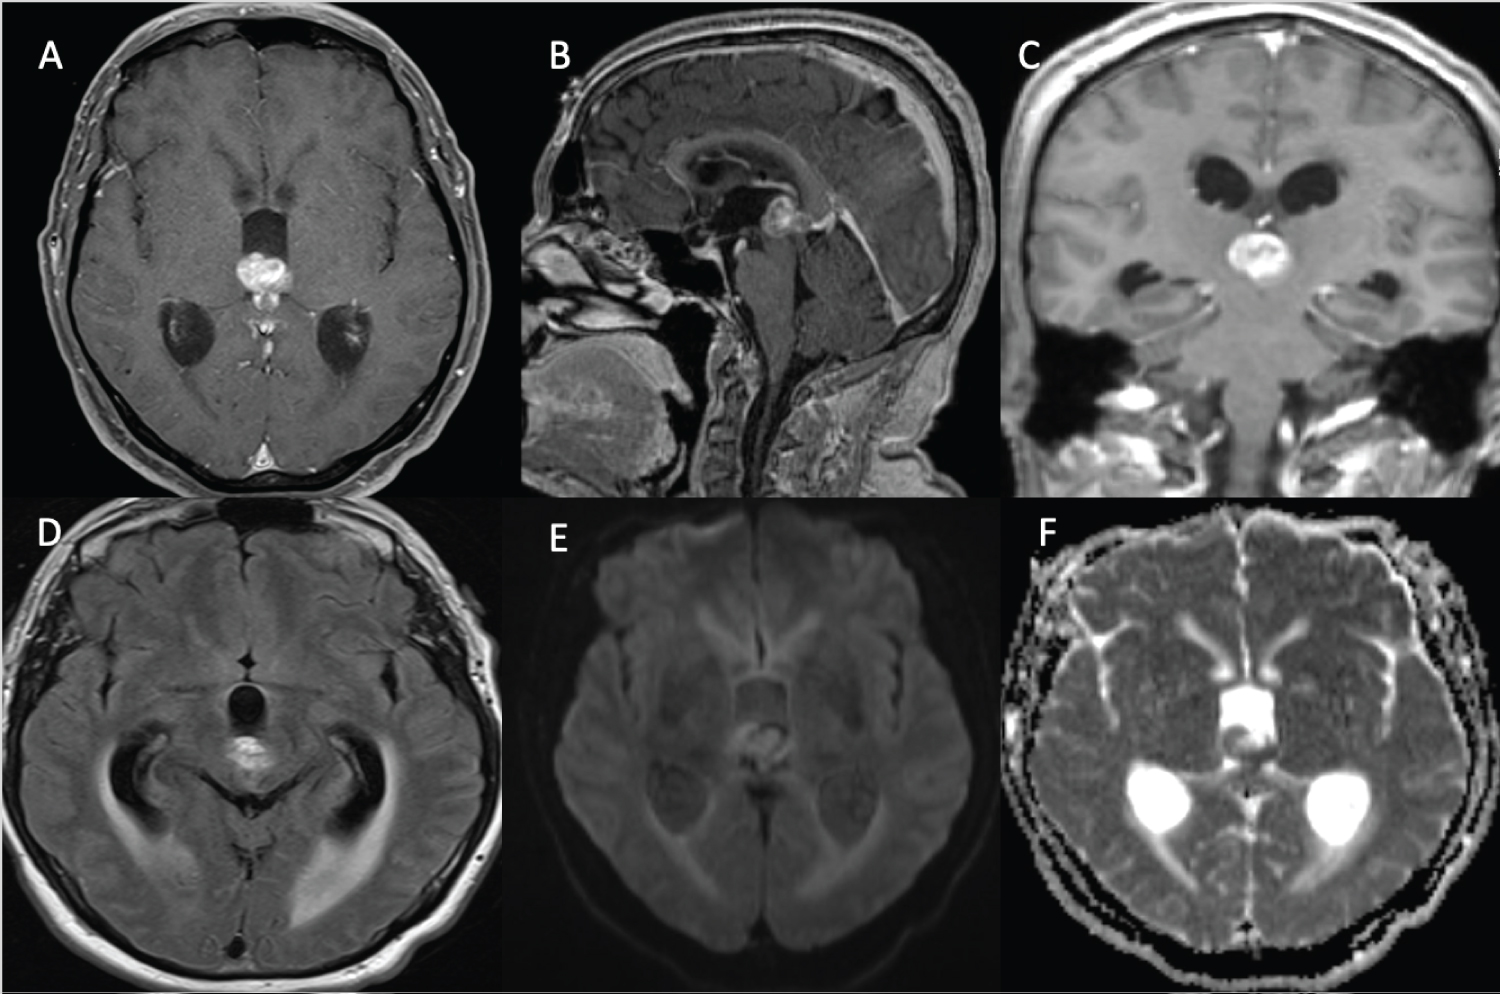

A 55-year-old male with a history of left thigh invasive melanoma resected a year ago with negative margins, presented to emergency department with a few days of severe headaches followed by urinary incontinence and decreased level of consciousness. Initial computerized axial tomography (CT) revealed a third ventricle/pineal region mass with effacement of the cerebral aqueduct with acute obstructive hydrocephalus. At the time of neurosurgical assessment, the patient was localizing and opening his eyes to noxious stimuli and making incomprehensive sounds. Given the poor neurological exam and the scan findings, an urgent right frontal external ventricular drain was inserted to decompress the patient's ventricles. Following stabilization, brain MRI with gadolinium was obtained which demonstrated a heterogeneously enhancing third ventricular/pineal region mass with obstruction of the aqueduct (Figure 1). Right frontal endoscopic third ventriculostomy with septostomy and biopsy of the mass was performed with image guidance. The tumor was extremely vascular, and the patient developed significant intraventricular hemorrhage which was managed with an external ventricular drain (EVD). A week later the EVD was removed and the patient was discharged neurologically intact.

Figure 1: Intraventricular/Pineal melanoma metastasis. (A, B & C) axial, sagittal and coronal T1 with GAD shows heterogeneously enhancing third ventricular/pineal region mass. (D) Axial FLAIR demonstrates mild ventriculomegaly with ballooning of third ventricles and trans ependymal flow secondary to the mass. (E & F) Axial diffusion-weighted imaging (DWI & ADC) demonstrates peripheral diffusion restriction. Findings are compatible with intraventricular/pineal region metastatic melanoma. View Figure 1